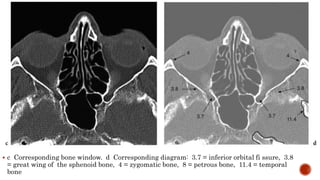

 a Axial CT at the inferior region of the orbit. b Corresponding diagram: 3.7 =

inferior orbital fi ssure, 3.12 = sphenoid sinus, 4.2 = temporal fossa, 9.1 = lens,

9.3 = sclera, 10.1 = inferior rectus muscle, 14.2 = internal carotid artery (ICA).

 c Corresponding bone window. d Corresponding diagram: 3.7 = inferior orbital fi ssure, 3.8

= great wing of the sphenoid bone, 4 = zygomatic bone, 8 = petrous bone, 11.4 = temporal

bone